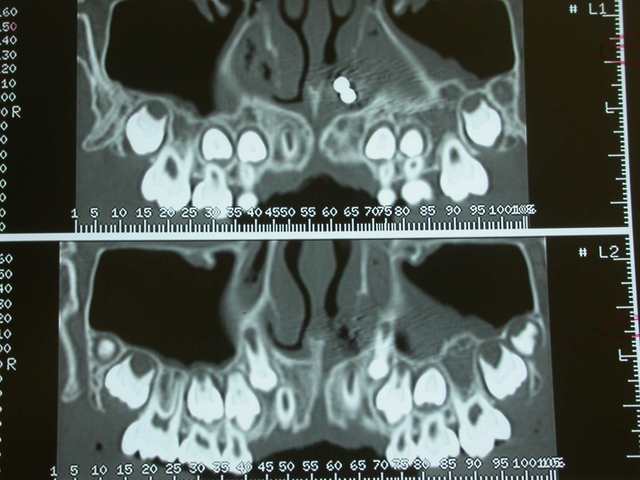

Je décide donc de faire réaliser un scanner et là c’est nouveau pour vous.

Une fois le scanner réalisé, je vois bien qu’il s’agit d’un objet composé de boules et l’adresse illico à son orl. Il la reçoit dans la foulée, et au vu du scanner, se refuse d’intervenir de peur de renvoyer plus loin l’objet. A son tour, il l’adresse à un hopital spécialisé enfants (Robert Debré). Au service ORL, ils tentent de retirer l’objet avec une pince (comme Dr House le faisait dans un épisode) et rien de neuf, aucune progression.